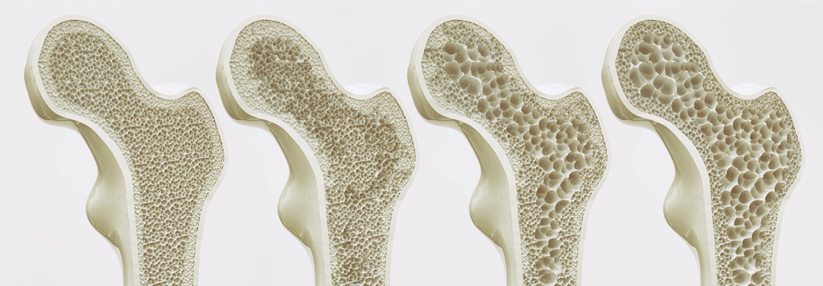

Vitamin D und Kalzium sind die Grundpfeiler jeder Osteoporosetherapie. Ein Experte erklärt, wann Sie die Behandlung um spezifische Antiosteoporotika ergänzen sollten und was dabei zu beachten ist.